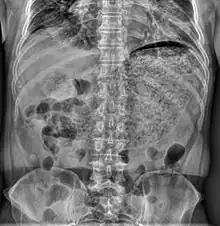

Simple abdominal X-ray reveals a large amount of material in the stomach, suggesting severe gastric hypomotility